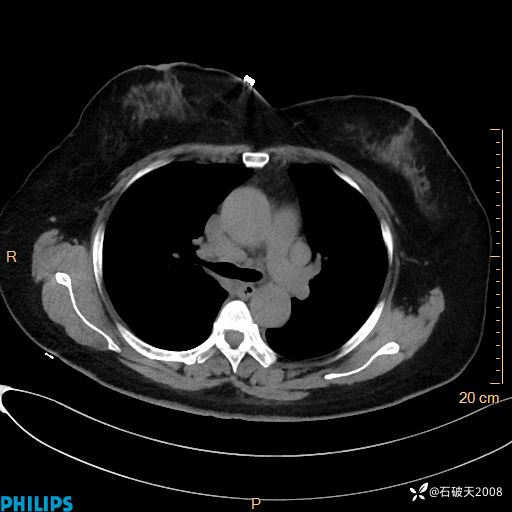

肺结节病?纵膈型肺癌?淋巴瘤?有点意思,欢迎围观

女 52岁 主 诉:咳嗽10余天,咳痰2天。

现病史:10余天前无明显诱因出现咳嗽,呈阵发性干咳,伴咽喉部发痒,无咽痛,无咳痰,无鼻塞、流涕、打喷嚏,无发热、畏寒、寒颤,无头痛、头晕,无胸闷、胸痛,无反酸、烧心,无腹痛、腹泻,无尿频、尿急,无皮疹等,在当地诊所求治,给予口服药物治疗(具体不详),病情无好转。遂在当地社区卫生服务中心开具口服药物治疗(具体不详),疗效欠佳。2天前出现咳痰,在我院门诊求治,行胸部CT提示肺部感染,建议住院,患者要求口服药物治疗,目前仍咳嗽、咳白色粘痰,白天量多,夜间自觉喉部喘鸣音,遂再次来院就诊,以“肺部感染”为诊断收入院。发病以来,神志清,精神可,饮食可,夜间睡眠差,大小便正常,近期体重无明显变化。

纵隔窗